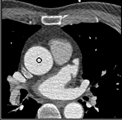

Samples for ascending aorta detection (black circle):

Cluster of candidate points in the ascending aorta.